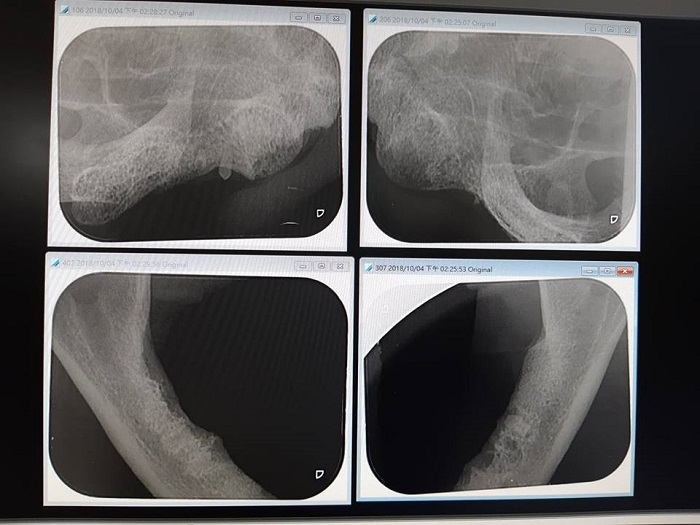

為治療貓咪口腔瘜肉,8/29至沐恩醫院檢查時發現血糖指數極高,因此再回到欣旺醫院開始施打胰島素治療,監控血糖指數變化,至10/4日血糖指數正常後至沐恩醫院進行熄肉切除,術後再至欣旺醫院接受照護觀察,並於10/14日狀況穩定後辦理出院。

10/4 進行口腔內牙周治療及熄肉切除,同時採樣送至台大動物醫院化驗。